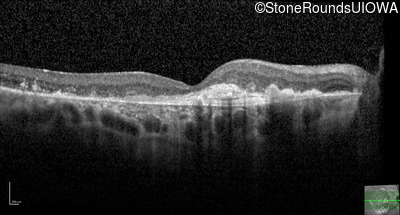

Age at visit: 59 years (Visit 3)